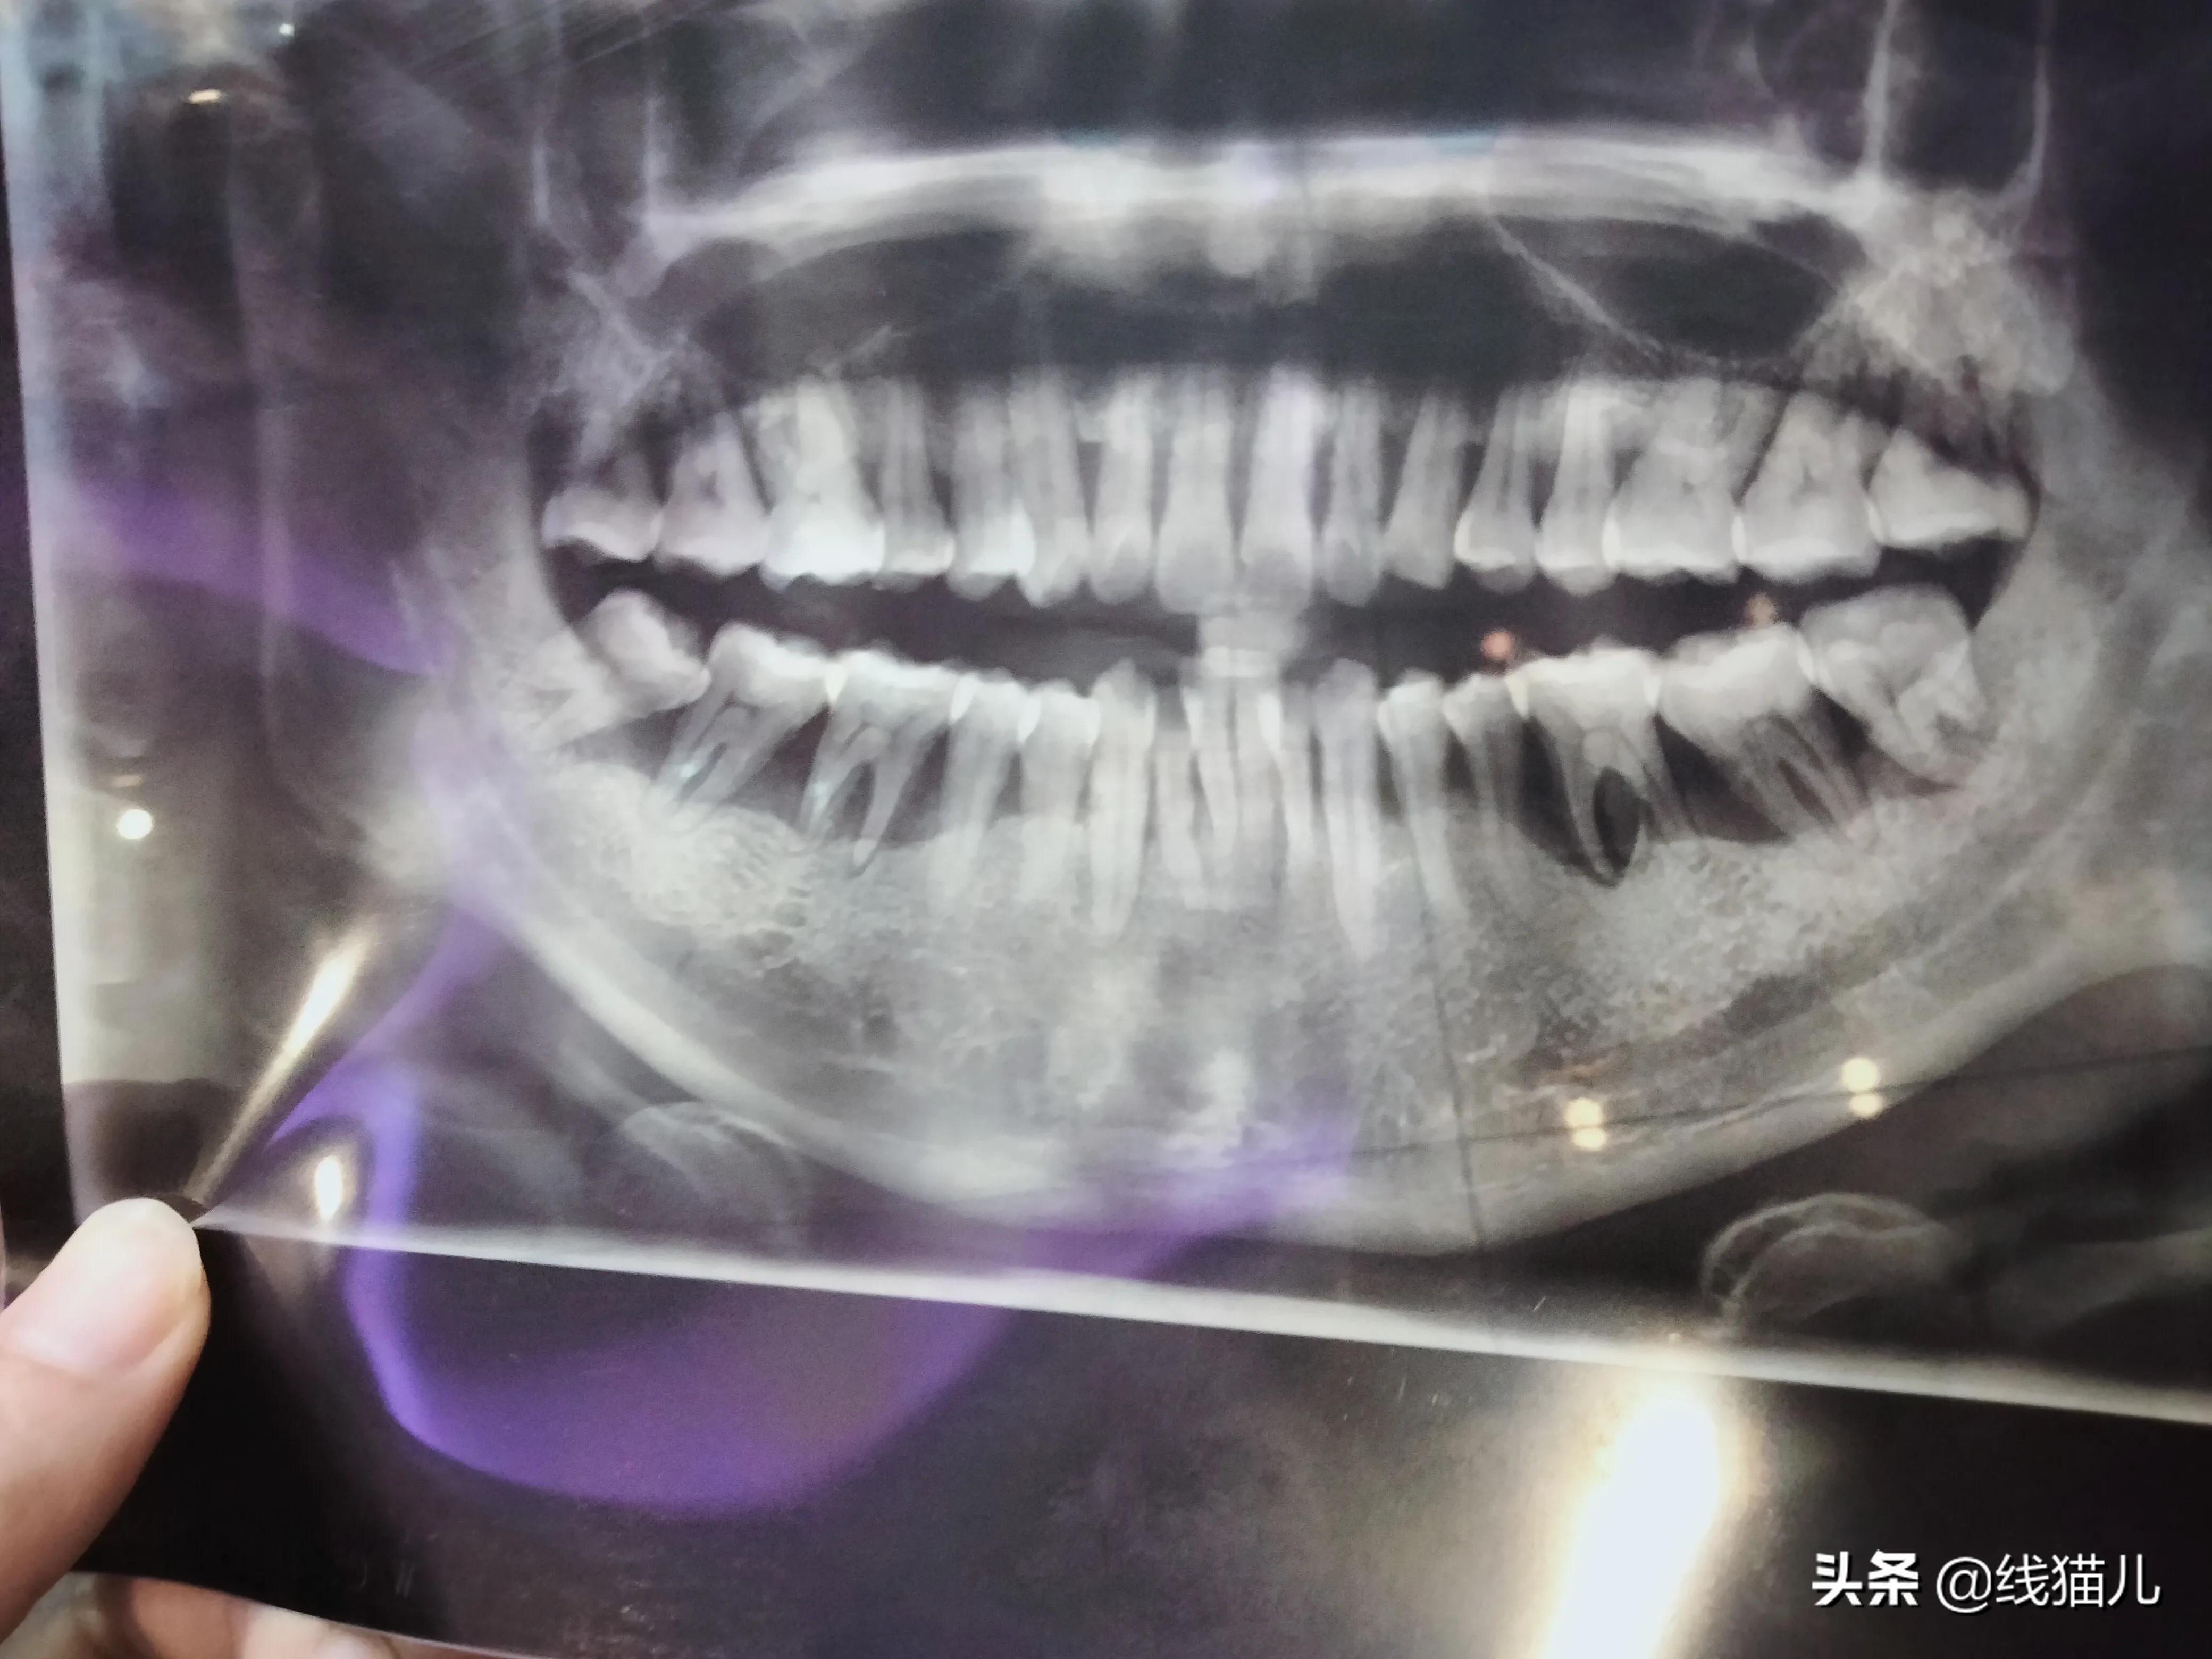

给你们看一下牙片,希望不会吓到你们。

专家就说我这很严重,特别是下排两侧……